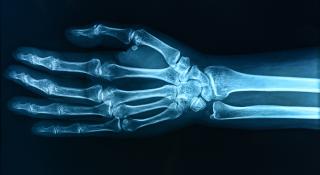

In zowel je pols als je hand(en) zitten verschillende gewrichten, pezen, zenuwen en spieren die ervoor zorgen dat je dagelijks kan functioneren en onder andere voorwerpen kan vastgrijpen. Problemen aan de pols en hand(en) kunnen verschillende oorzaken hebben, zoals een val of ongeluk. Maar ook dagelijkse activiteiten kunnen de aanleiding zijn voor bepaalde pols- of handaandoeningen.